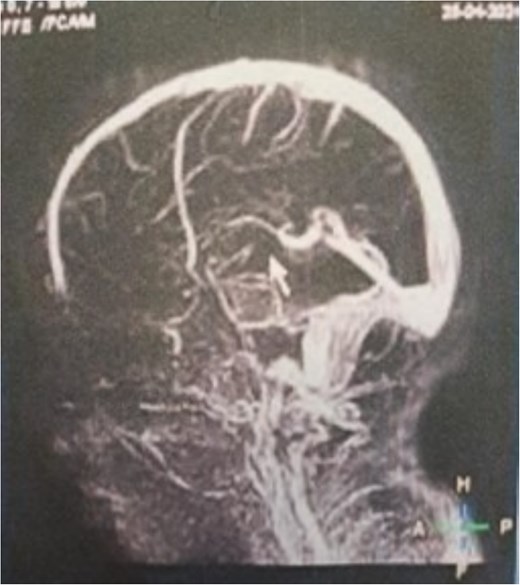

Additionally, magnetic resonance venography (MRV) confirmed a patent superior sagittal sinus with no encroachment of the lesion (Fig. 4). Differential diagnoses included dermoid cyst, eosinophilic granuloma, or benign fibro-osseous lesion. Surgical intervention involved en bloc excision under general anesthesia. A curvilinear incision was made over the mass, followed by subperiosteal dissection, which confirmed the lesion’s confinement to the diploë. Intraoperative frozen section analysis was not performed due to the lesion’s benign radiological features. Histopathological examination confirmed NOF, demonstrating ectodermal inclusion, cellular stroma of spindle-shaped fibroblasts arranged in a prominent storiform pattern, and scattered osteoclast-like giant cells. Notably, no evidence of mitotic figures, nuclear atypia, or necrosis was observed (Figs 5–7). The margins were free of lesional tissue. Postoperatively, the child resumed oral intake within 4 hours and was discharged on postoperative day 2 with analgesics. At the 6-month follow-up, the wound had healed without complications, with no recurrent lesion.

MRV sagittal view showing patent superior sagittal sinus with no encroachment of the lesion.

The diagnostic complexity of cranial NOF is underscored by its potential to mimic malignant processes on functional imaging. Pagano et al. demonstrated that NOFs in long bones can exhibit significant F18-FDG avidity on PET/CT, erroneously suggesting metastatic involvement in lymphoma patients—a critical interpretive pitfall requiring correlation with anatomical imaging [6]. This metabolic activity, likely reflecting osteoblastic activation during lesion involution, further complicates the assessment of atypical sites like the skull, where benign entities may simulate aggressive pathology. Epidemiologically, our case aligns with the male predominance observed in large cohort studies. Emori et al.’s survey of 6222 Japanese children revealed NOF prevalence of 2.6% in boys versus 2.1% in girls, suggesting biological sex differences in lesion development [10]. Interestingly, their data showed peak NOF incidence at age 14—contrasting with our preschool-aged patient—highlighting that cranial lesions may follow distinct chronological patterns compared to appendicular skeletons. The biological behavior of NOF also warrants consideration. While Herget et al. established that stage B lesions in long bones carry the highest fracture risk (75% transverse diameter involvement in fractured cases) [13], cranial NOFs likely follow different biomechanical principles. The occipital location in our case spared weight-bearing function but posed unique risks due to proximity to dural sinuses, necessitating preoperative MRV assessment to exclude venous compromise. Finally, the epiphyseal involvement documented by Noh et al. [12]—previously considered exceptionally rare—parallels our case’s deviation from classical metaphyseal predilection, suggesting NOFs may exhibit greater anatomical plasticity than historically recognized.